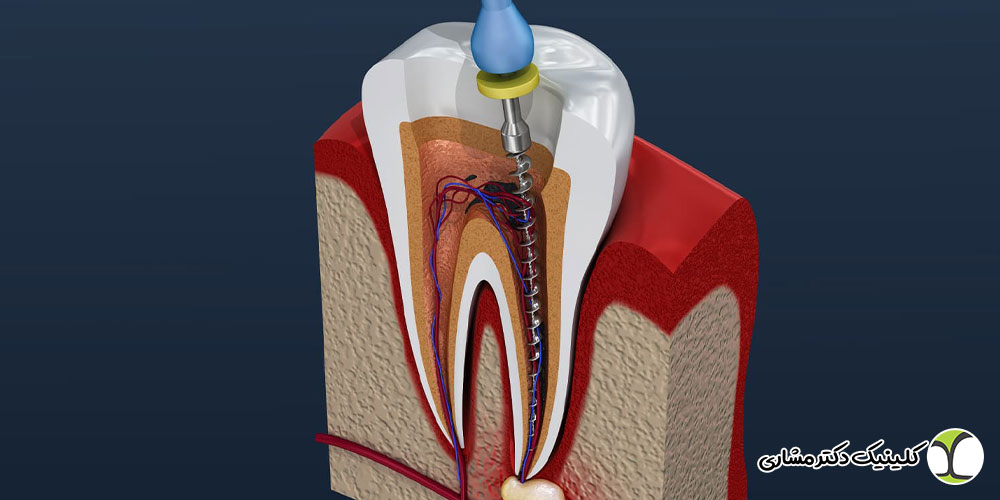

درمان مجدد ریشه یا ری اندو، فرایندی است که طی آن دندان قبلاً عصبکشی شده دوباره باز می شود و مواد پرکردگی کانال ها خارج شده، کانال ها پاکسازی و ضدعفونی شده و مجدداً پر می شوند.

این فرایند معمولاً توسط متخصص اندودنتیست انجام می شود و به دلیل پیچیدگی آن، نیازمند تجهیزات پیشرفته و مهارت بالای دندانپزشک است. هدف اصلی درمان مجدد رفع عفونت و اصلاح مشکلات درمان اولیه است تا دندان حفظ شود و نیازی به کشیدن آن نباشد.

آمادگی و برنامه ریزی درمان: اگر درمان مجدد ریشه انتخاب شود، معمولاً ابتدا پوسیدگی ها و ترمیم های قبلی برداشته می شوند و مسیر ورود به کانال ها ایجاد می گردد. سپس مواد پرکردگی قدیمی خارج شده و کانال ها با وسایل مخصوص شکل دهی و تمیز می شوند تا عفونت و باکتری ها به طور کامل از بین بروند.

پر کردن مجدد کانال ها و ترمیم تاج دندان: پس از پاکسازی کامل کانال ها، آنها با مواد مخصوص (مثل گوتاپرکا) پر می شوند تا ورود میکروب ها به کانال مجدد غیرممکن شود. در نهایت تاج دندان پانسمان شده و برای ترمیم نهایی یا قرار دادن روکش به دندانپزشک مربوطه ارجاع داده میشود.

پیگیری و معاینات دوره ای: پس از اتمام درمان مجدد، لازم است بیمار تحت پیگیری دوره ای قرار گیرد. معاینات کلینیکی و رادیوگرافی در بازه های ۶ ماه، یک سال و دو سال پس از درمان انجام می شود تا اطمینان حاصل شود دندان سالم و بدون عفونت باقی مانده است.